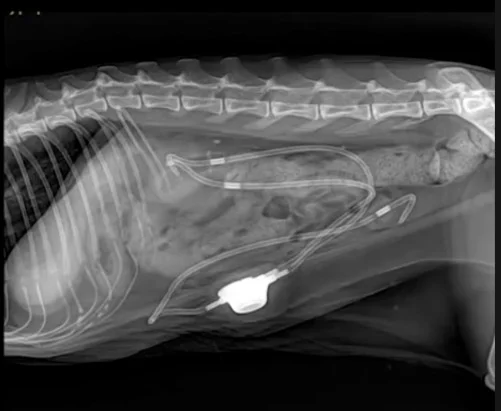

BYPASS (vista latero-lateral)